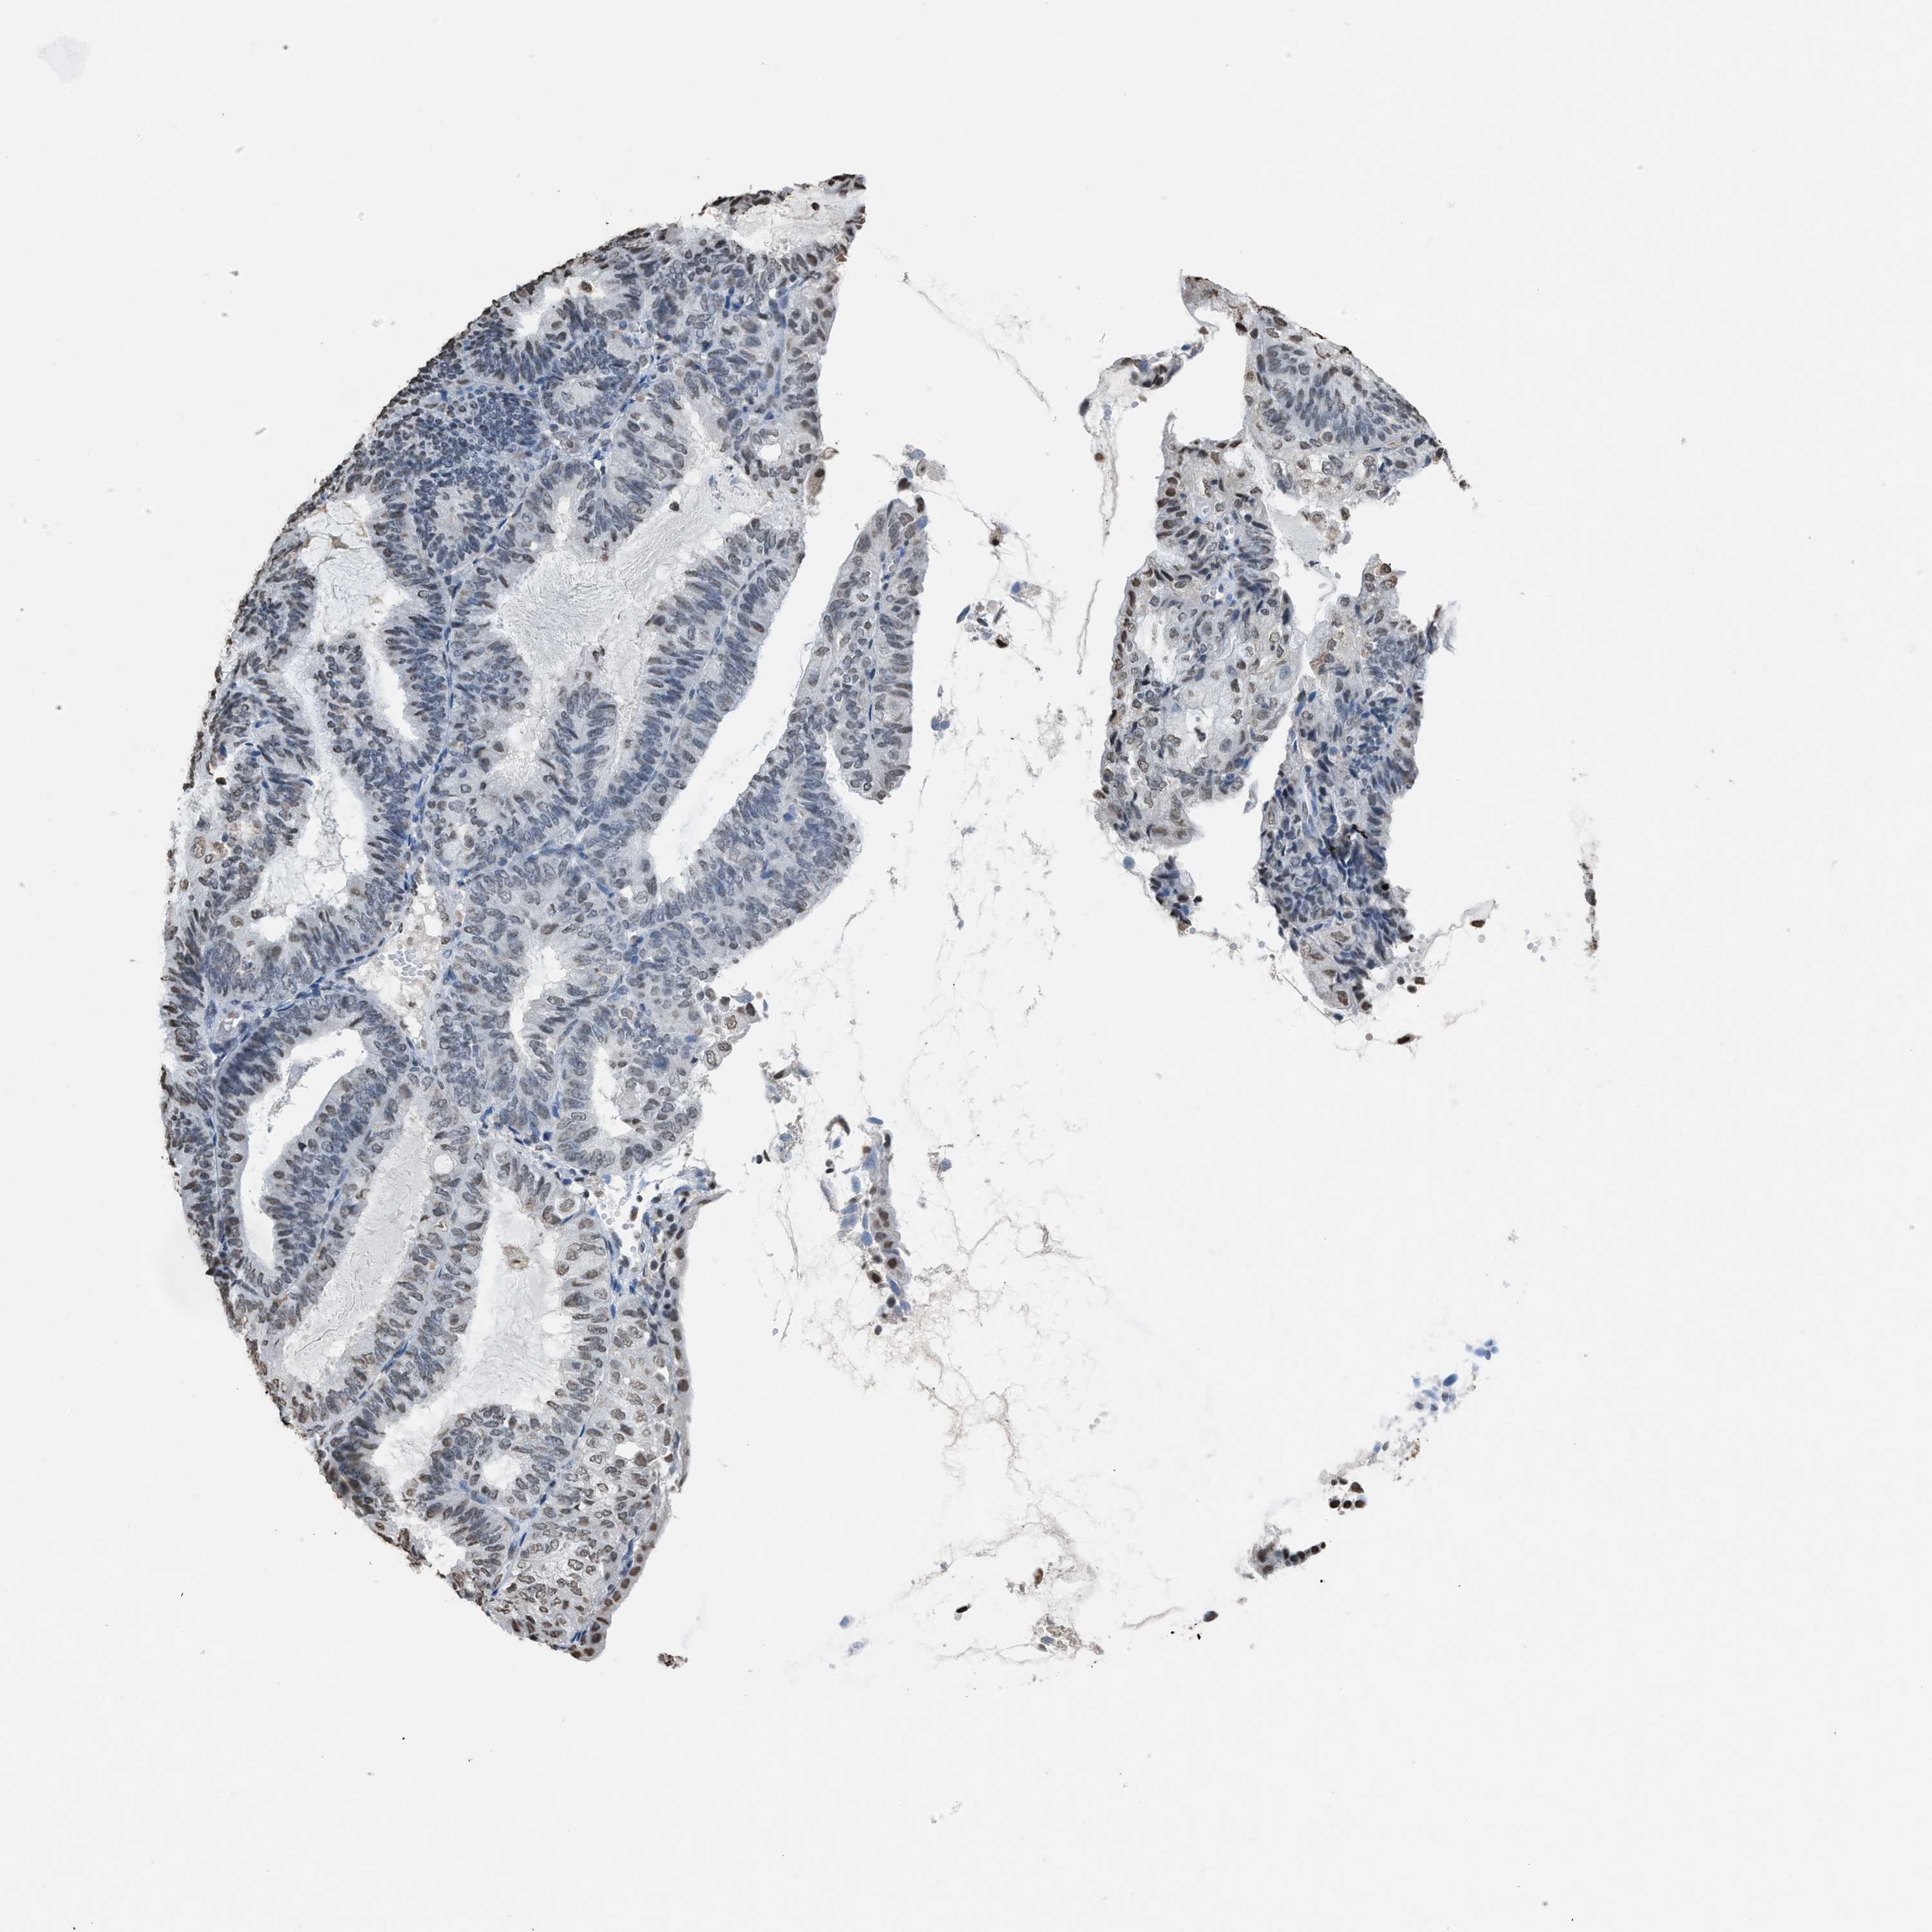

ENDOMETRIAL CANCER - Protein expressioni

A mouse-over function shows sample information and annotation data. Click on an image to view it in a full screen mode. Samples can be filtered based on level of antibody staining by selecting one or several of the following categories: high, medium, low and not detected. The assay and annotation is described here.

Note that samples used for immunohistochemistry by the Human Protein Atlas do not correspond to samples in the TCGA dataset.

Antibody stainingi

Antibody staining in the annotated cell types in the current human tissue is reported as not detected, low, medium, or high, based on conventional immunohistochemistry profiling in selected tissues. This score is based on the combination of the staining intensity and fraction of stained cells.

Each image is clickable and will lead to virtual microscopy that enables deeper exploration of all samples and also displays staining intensity scores, fraction scores and subcellular localization as well as patient and tissue information for each sample.

Antibody HPA021816

Antibody CAB002209

Staining

High

Medium

Low

Not detected

Intensity

Strong

Moderate

Weak

Negative

Quantity

>75%

75%-25%

<25%

None

Location

Nuclear

Cytoplasmic/membranous

Cytoplasmic/membranous,nuclear

Adenocarcinoma, NOS

Adenoma, NOS

Neoplasm, malignant, NOS